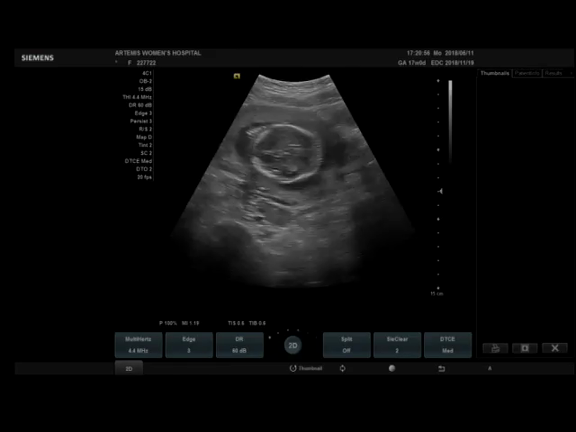

2910 · エコー写真の性別予想ジンクスは本当? 写真の見方や性別の見分け方 妊娠中の超音波検査でエコー写真をもらうことがあるでしょう。エコー写真は赤ちゃんの様子を確認することができますし、いつまでも保管していきたいものですよね。妊 panda 医療監修妊娠5ヶ月の妊 · 性別はいつから分かる? ジンクス的(お腹の膨らみ方、顔つきといった人によって印象が違うもの)を除き、11~12週頃の横向きのエコー写真で判別する「Baby nub」という判別方法があ0112 · 写真の見方や保管のポイント2:性別がわかる時期は? 外性器がはっきり写っていれば赤ちゃんの性別がわかりますが、赤ちゃんの位置や体勢によって外性器が見えにくい場合もあるので、必ずわかるわけではありません。 早ければ12週から15週のエコー検査で性別がわかることもあります

0115 · 写真の見方や性別の見分け方 エコー写真は赤ちゃんの様子を確認することができますし、いつまでも保管していきたいものですよね。 妊娠週以降になると、場合によっては赤ちゃんの性別を確認することができるようになります。25 · 妊娠15週目の超音波検査では、胎児の性器がはっきりとし始め、性別を調べられる場合があります。 性別は、妊娠週頃になるとより確認しやすくなる でしょう。